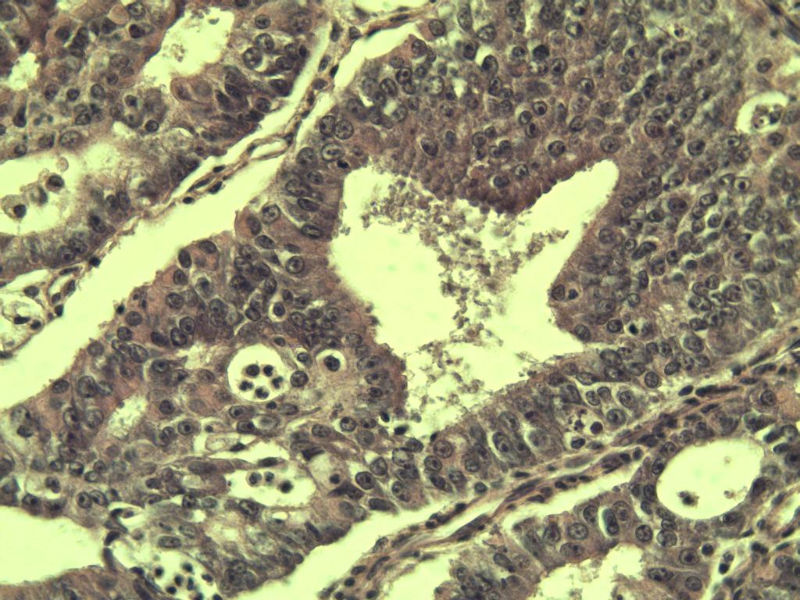

女 32岁 不规则阴道流血 一年  请各位老师看看 谢谢了

遵义医学院附属医院会诊结果    "复杂性增生伴非典型性 "

补充一下病史 病人10个月前因月经不规则行诊刮 诊断非典型性增生  上了曼月乐避孕环(好像是缓慢释放孕激素的那种),         都用激素治疗大半年了 还是这个样子 我还是觉得是癌  只有追踪一下以后病人的情况吧

高分化子宫内膜样癌

非典型复杂性子宫内膜增生,应了解雌孕激素情况。

子宫内膜复杂性非典型性增生,局灶区间质肉芽样(图5)及蜕膜样变,不够癌,建议临床查激素水平并追踪。

从照片看,没看到浸润的地方,我考虑是子宫内膜重度不典型增生。